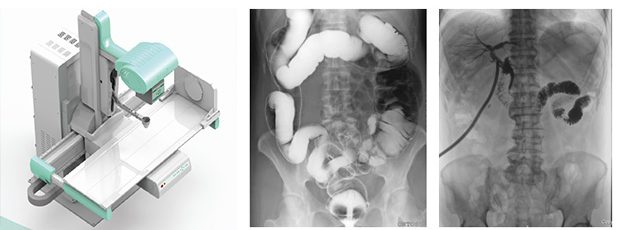

DR是數(shù)字化直接成像系統(tǒng)的簡(jiǎn)稱,也常寫(xiě)作Dr,是指在計(jì)算機(jī)控制下直接進(jìn)行數(shù)字化X線攝影的一種新技術(shù),即采非晶硅平板探測(cè)器把穿透人體的X線信息轉(zhuǎn)化為數(shù)字信號(hào),并由計(jì)算機(jī)重建圖像及進(jìn)行一系列的圖像后處理。那動(dòng)態(tài)DR是什么DR呢?從其宣傳看首先它是個(gè)DR,可以做數(shù)字?jǐn)z影,其次它可以透視點(diǎn)片,可以進(jìn)行消化道造影及泌尿系統(tǒng)造影,并可以進(jìn)行治療引導(dǎo)。

動(dòng)態(tài)DR可以從不同的角度、時(shí)間來(lái)觀察器官的運(yùn)動(dòng),診斷準(zhǔn)確率會(huì)大大提升。其實(shí)動(dòng)態(tài)DR的多角度檢查,其視覺(jué)效果上有點(diǎn)類似于CT。

動(dòng)態(tài)DR所采用的數(shù)字探測(cè)器,全幀技術(shù)可以得到盡量大的光電二極管,能夠輸出更穩(wěn)定清晰的影像質(zhì)量。數(shù)字高壓技術(shù)具有高壓快門,能夠在毫秒級(jí)時(shí)間內(nèi),實(shí)現(xiàn)高壓的切換。采用雙通道算法以及并行圖像處理技術(shù)。動(dòng)態(tài)dr的探測(cè)器為17*17 ,完全可以在同一個(gè)屏幕中獲取整個(gè)檢查部位的視野,便于觀察。

其次采用動(dòng)態(tài)dr視頻采集技術(shù),經(jīng)過(guò)一次順利的檢查后保存視頻,可以實(shí)時(shí)回顧分析采集圖像,也有利于疾病的隨訪、對(duì)比及會(huì)診。此外,在骨科診斷過(guò)程中,由于隱匿性骨折范圍小、程度輕,即使使用ct檢查敏感性也不高,mri檢查費(fèi)用過(guò)于昂貴,而用動(dòng)態(tài)DR透視下的多軸位點(diǎn)片,可以明確隱匿性骨折的診斷,是避免誤診隱匿性骨折的有效辦法之一。

動(dòng)態(tài)DR對(duì)某些重疊病灶的診斷有著極高的臨床意義,在常規(guī)DR所拍攝的靜態(tài)片中很難區(qū)分重疊病灶是處在什么位置及哪個(gè)器官上,而通過(guò)動(dòng)態(tài)觀察可以清晰的判斷和診斷。